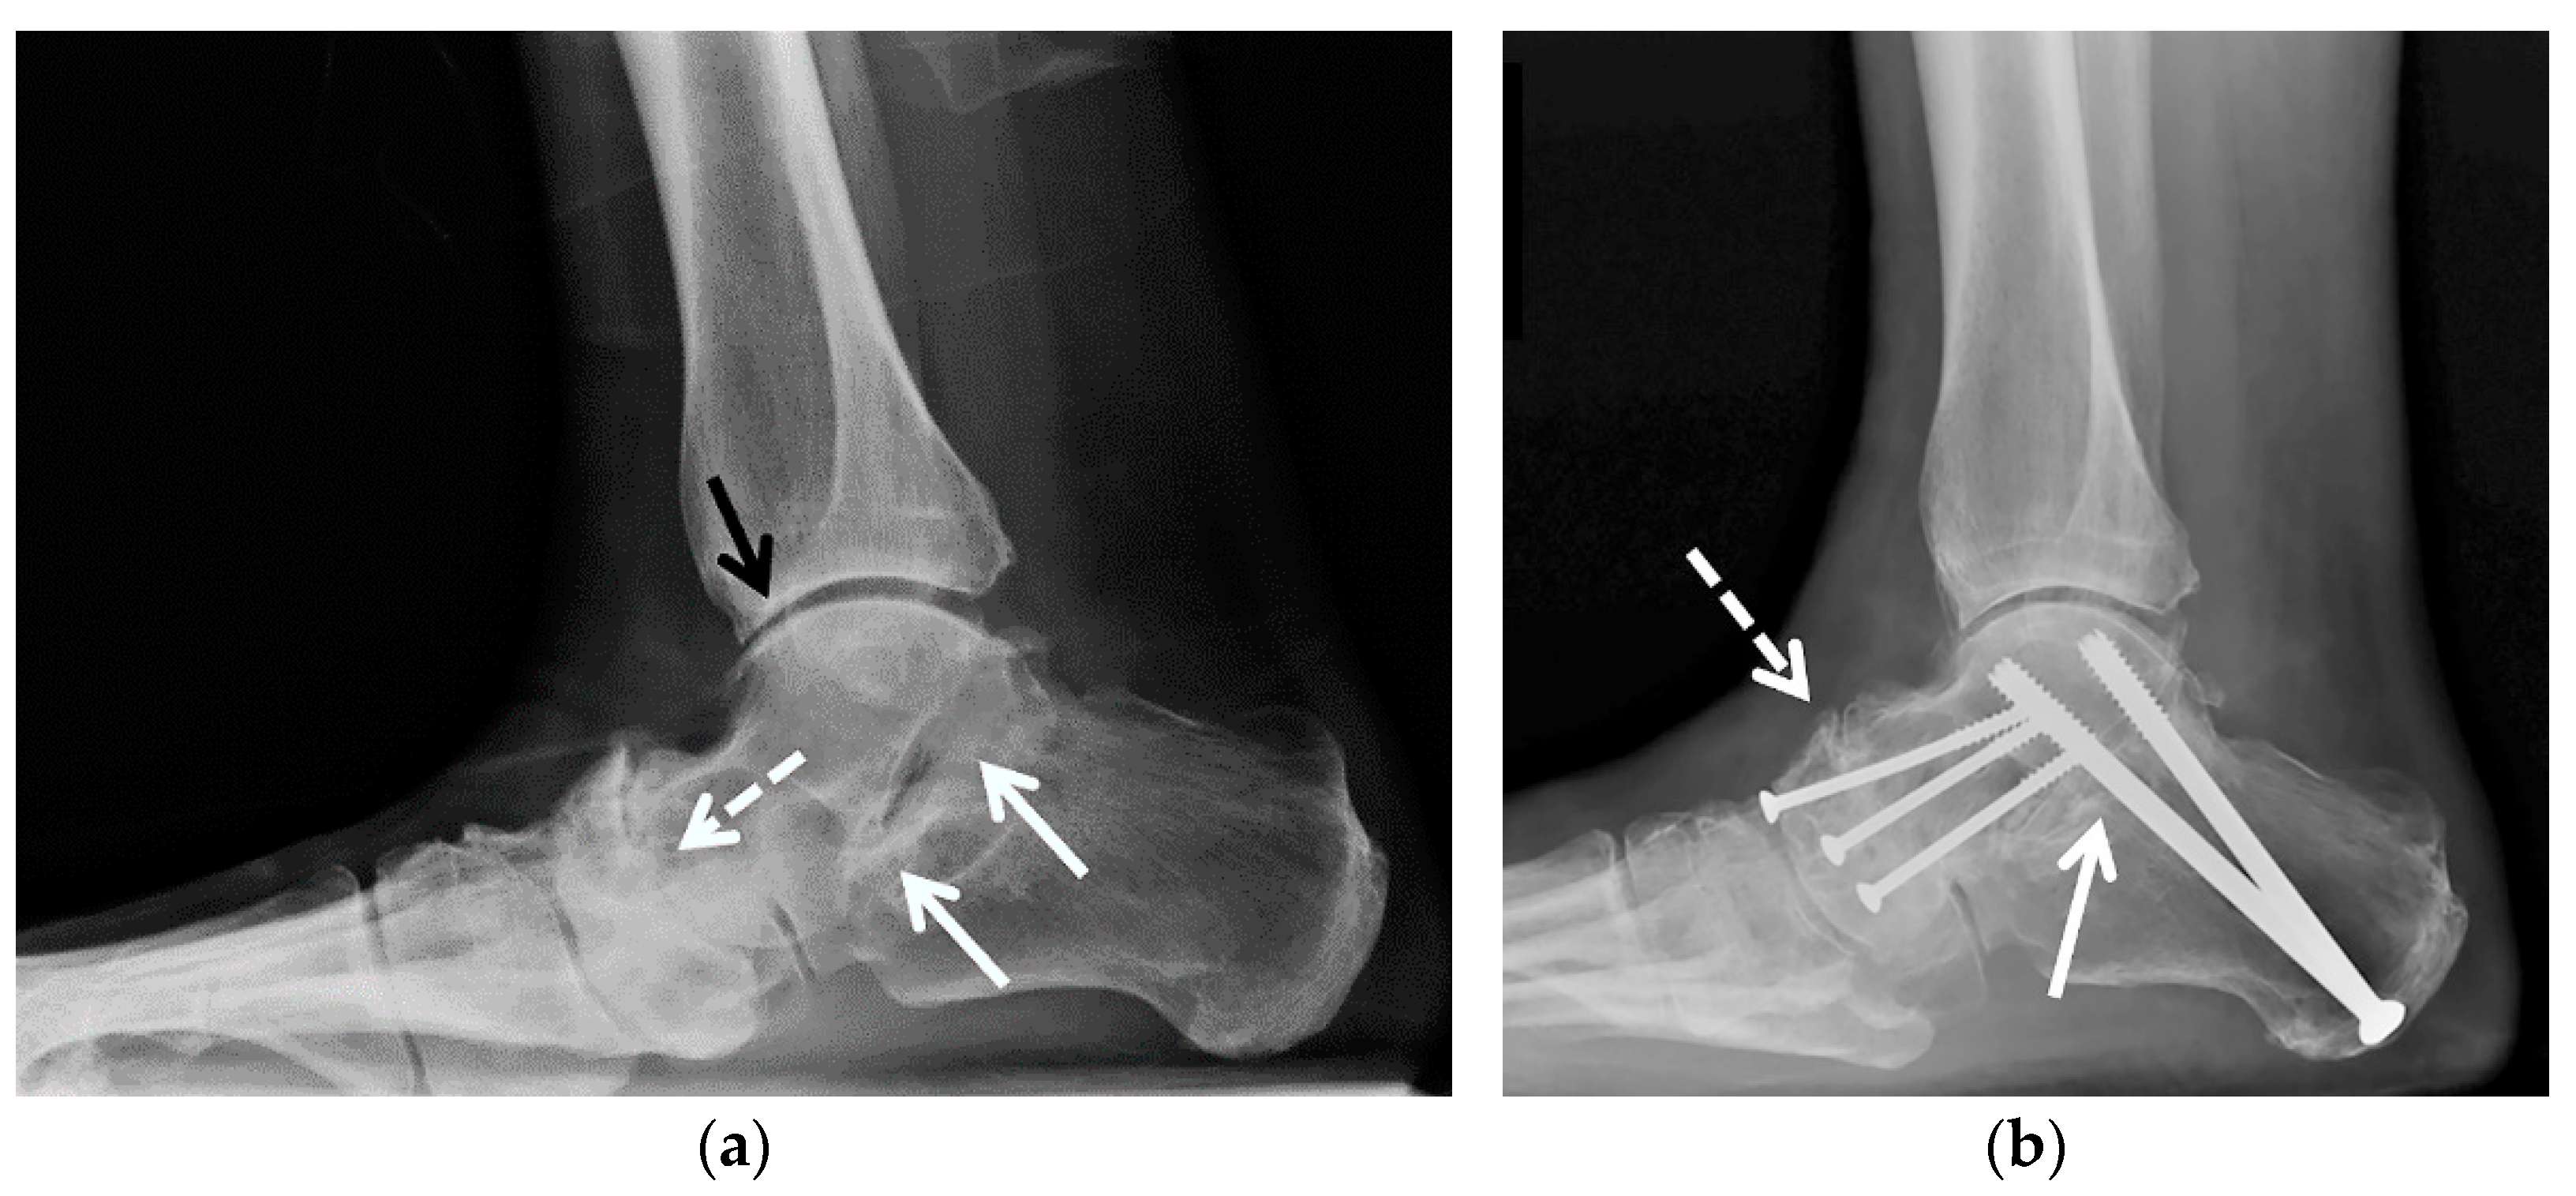

5.2.1. Joint-Preserving Procedures

5.2.2. Arthrodesis